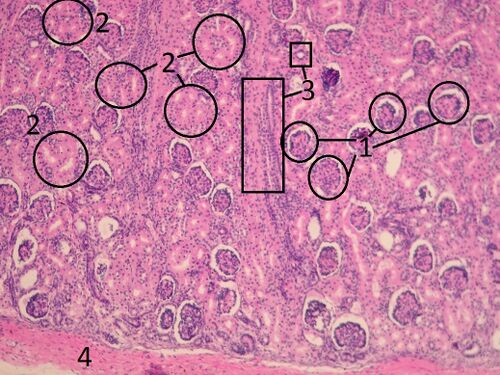

Name: Renal cortex (HE)

1 – kidney bodies (glomerulus and Bowmann's capsule)

2 – proximal tubules (larger and more eosinophilic)

3 – distal tubules

4 – fibrous capsule of the kidney